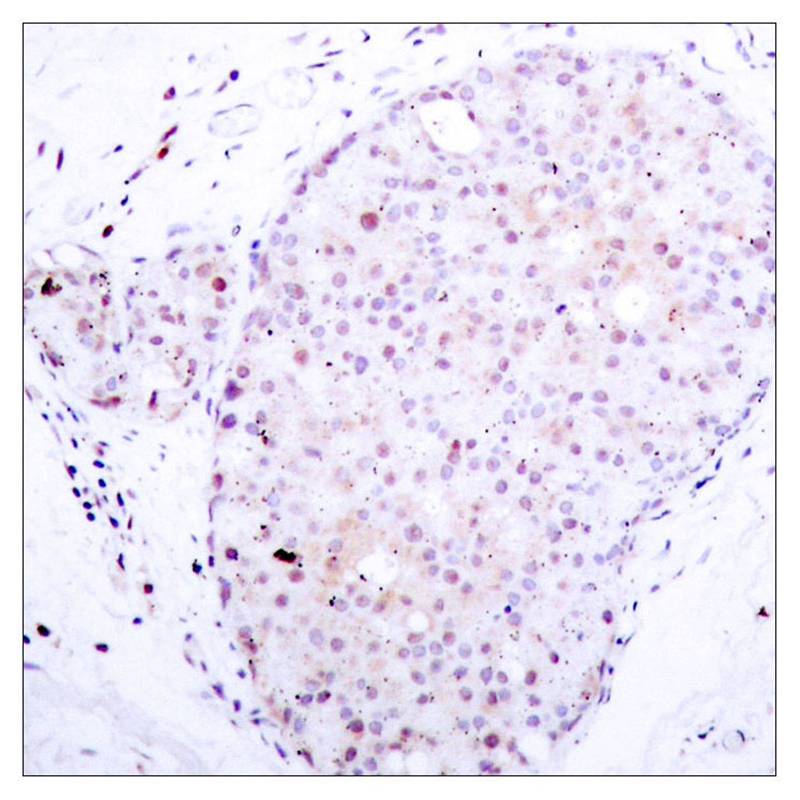

Product Image

| IHC | 1/50-1/100 |